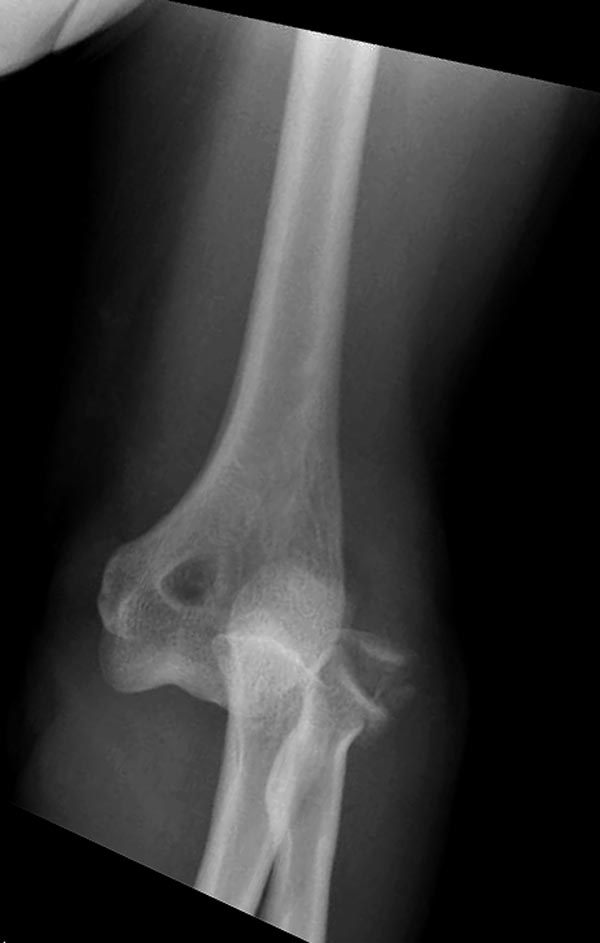

Вместе обычных простых рентгенограм, участились злоупотребления дорогими исследованиями. Хотя многие переломы, даже внутрисуставные, можно увидеть на обычных рентген снимках. Негативный рентген при исследовании локтевого сустава не означает отсутствие перелома. Если имеется “fat pad sign”, характерный симптом для внутрисуставных повреждений, тогда можно ставить диагноз перелом головки луча! Гематома внутрисуставного перелома смещает жировое тело и на боковом снимке проявляется в виде “паруса”.

На переломы головки луча надо обратить внимание, потому что головка луча является важным стабилизатором в локтевом суставе: удерживает от заднего вывиха и от боковых смещений. Изолированный перелом головки луча встречается очень редко и, в основном, в сопровождении с другими повреждениями, вывихом сустава, переломом Monteggia, венечного отростка или повреждением латерального лигамента.

Здесь представлены несколько случаев и как видно больше больных с серьезными повреждениями, чем изолированные..

В первом случае перелом Монтеджи, где доперационно сделано оценка положения головки к остальным элементам под рентгеном. Учитывая правильность взаимотношении произведена фиксация только локтевого отростка, Второй случай, заменена на протез, и третий, кроме фиксации головки - реконструкция capitellum латерального мыщелка.